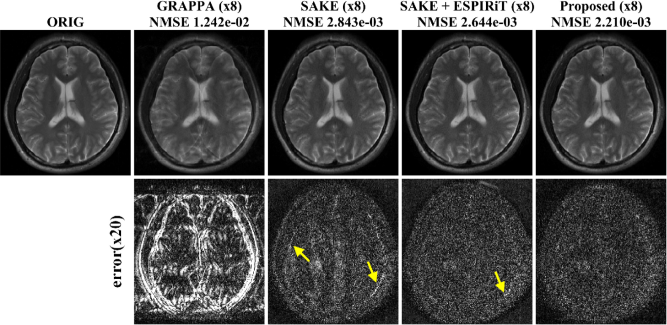

Refer to caption

Figure 5: Reconstruction results from 8 fold accelerated k-space data using (a) single coil and (b) four coils data set. Purple lines denote the regions corresponding to y-t cross sections that are magnified along temporal axis. The second rows in both (a) and (b) show the difference images between the ground-truth and the reconstructions.

Using the sub-sampled k-space data at the acceleration factor of eight, the average NMSE values of k-t FOCUSS, LORAKS, and ALOHA, were 1.616×1021.616superscript1021.616\times 10^{-2}, 1.363×1021.363superscript1021.363\times 10^{-2}, and, 1.151×1021.151superscript1021.151\times 10^{-2}, respectively. The sub-sampled data was collected according to a Gaussian distribution and included the four center lines around zero frequency. The average NMSE values were calculated using all temporal frames. These results confirmed that the proposed method outperformed k-t FOCUSS and LORAKS. As shown in Fig. 5(a), the temporal profile (indicated as a broken purple line) of the proposed reconstruction provided more accurate structures especially in the systole phase that were comparable to the true one, whereas the temporal variation in the k-t FOCUSS and LORAKS reconstruction became smoother and more blurry along the temporal dimension.

The NMSE values of the parallel dynamic imaging results from k-t FOCUSS, SAKE, and the proposed method using four coil k-space data were 8.75×1038.75superscript1038.75\times 10^{-3}, 4.983×1034.983superscript1034.983\times 10^{-3} and 3.436×1033.436superscript1033.436\times 10^{-3}, respectively, which quantitatively showed that the proposed method outperformed k-t FOCUSS and SAKE. Reduced residual artifacts were perceivable in the ALOHA difference images in Fig. 5(b). Moreover, the temporal profiles of the proposed reconstruction showed more accurate structures which were comparable to the true one, whereas the dynamic slice profile from k-t FOCUSS and SAKE showed smoother and more blurry transition. In particular, the proposed algorithm resulted in more accurate reconstructions of dynamic changes at the heart wall in the systole phase as shown in Fig. 5(b).